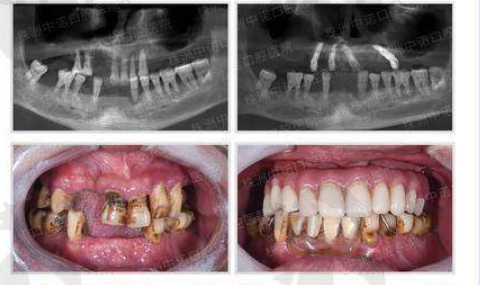

我这牙齿啊,一直都不太好。年轻的时候就爱吃甜食,还不咋注意口腔卫生,结果年纪轻轻就开始掉牙。一开始掉一两颗的时候,我也没太在意,觉得不影响啥。可后来掉的牙越来越多,半口牙都快没了,这问题就来了。

吃饭的时候那叫一个费劲,稍微硬一点的东西都咬不动,只能吃点软乎乎的粥啊、面条啥的。时间长了,营养都跟不上,整个人气色也不好。而且说话还漏风,一开口“嘶嘶”的,特别影响形象。我试过戴假牙,可那玩意儿戴着真不舒服,还老是掉,别提多闹心了。

给我看牙的就是黎强院长。黎院长人特别和蔼可亲,他先仔细地给我检查了牙齿,又问了我的一些生活习惯和需求。然后跟我详细地解释了种植牙的原理、过程和注意事项。他说我这种半口牙齿缺失的情况,做半口速齿种植牙挺合适的。

我有点担心价格这么低,成效会不会不好。黎院长好像看出了我的顾虑,他跟我确保,他们用的都是正规的种植体,技术也是成熟可靠的,让我放心。而且还给我看了特别多之前患者的实例,看着那些患者种完牙后笑得那么灿烂,我心里的顾虑一下子就打消了。